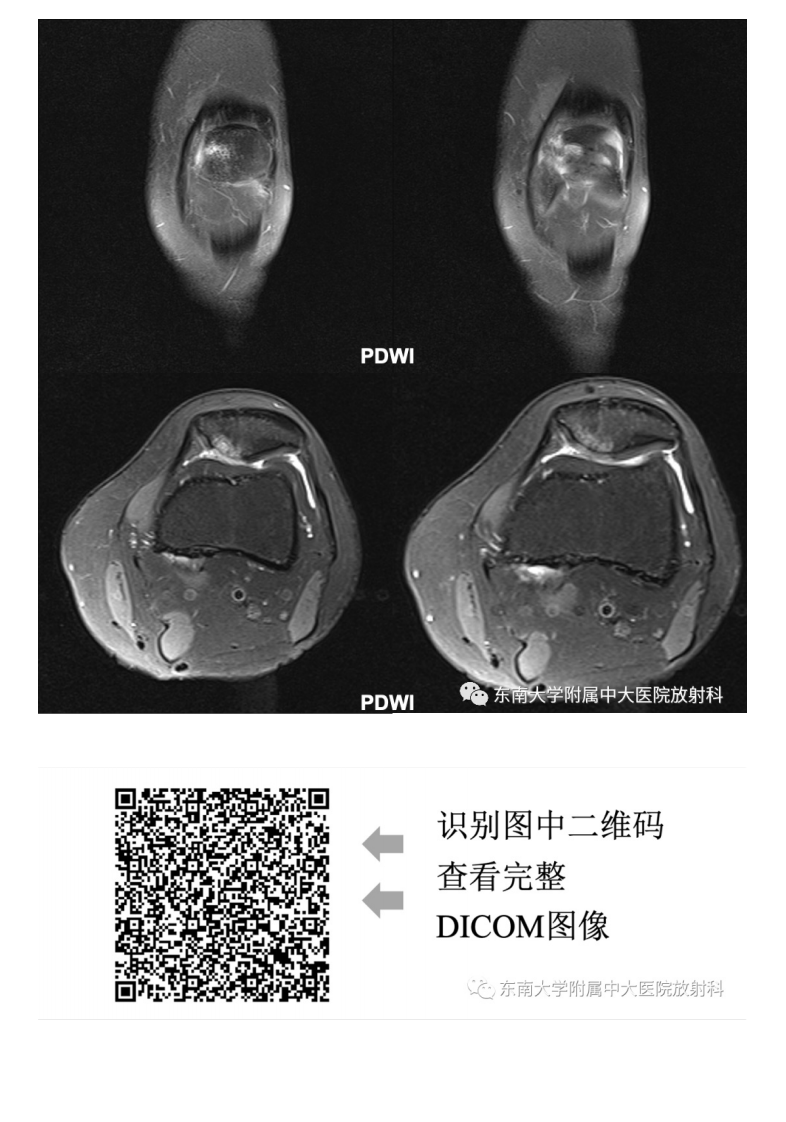

20210506_3【晨读结果公布】2021.05.06肌骨系统疾病——髌骨软化症.pdf